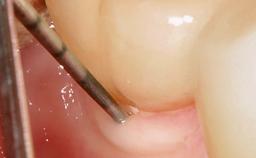

In this case, Myroslav Solonko, Ignacio Sanz Sánchez and Mariano Sanz present a treatment that aims to eliminate exposed implant threads by modifying the implant surface, converting a moderately-rough surface into a smooth surface.

A 63-year-old male patient was referred to the post-graduate periodontal clinic of the Complutense University of Madrid for the treatment of peri-implantitis. According to the patient’s record, all his maxillary teeth had been extracted ten years previously due to severe periodontitis, and a full-mouth implant-supported restoration on eight implants was placed. No supportive periodontal therapy was provided apart from occasional check-ups by the restorative dentist.